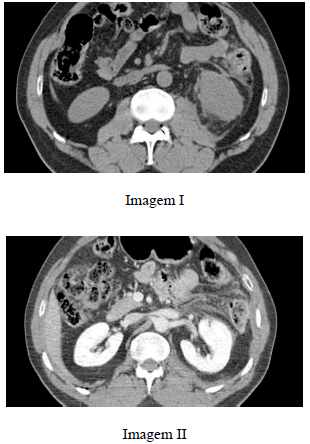

Paciente do sexo masculino, com 37 anos de idade, após cair de uma árvore de 6 m de altura, refere dor lombar à esquerda e hematúria. Realizou tomografia computadorizada de abdome, que evidenciou as imagens I e II a seguir.

Enunciado 3064448-1

Com base nesse caso clínico, julgue o item subsecutivo.

Observa-se isquemia do rim esquerdo, provavelmente relacionada à avulsão da artéria renal correspondente.